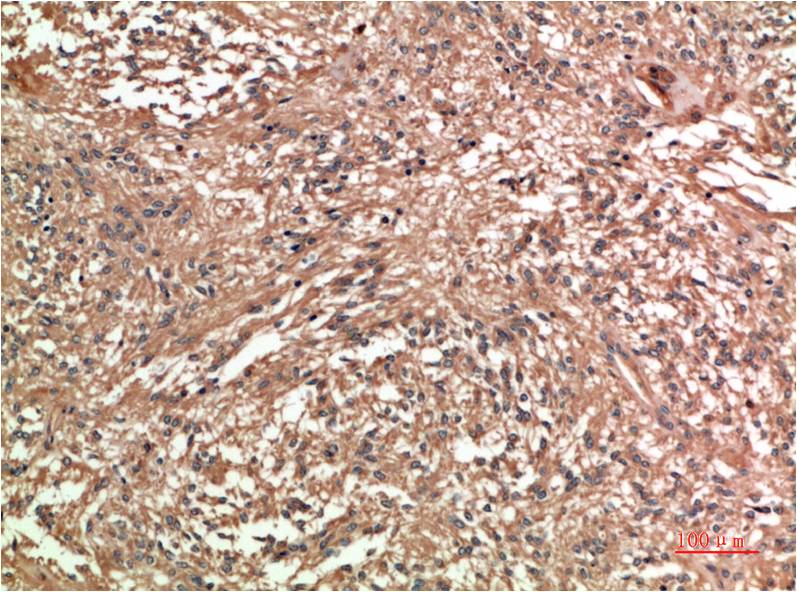

c-Jun Mouse Monoclonal Antibody(4G10)

Applications :IHC

| Recommended dilutions: | IHC 1:100-200 |

| Specificity: | The c-Jun Mouse Monoclonal Antibody can detects endogenous c-Jun proteins. |